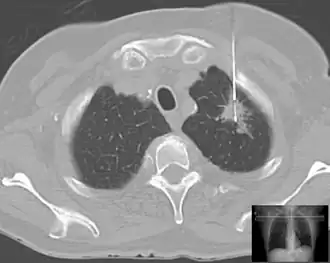

Lung biopsy in a case of suspected lung cancer under control of computed tomography.

When cancer is suspected, a variety of biopsy techniques can be applied. An excisional biopsy is an attempt to remove an entire lesion. When the specimen is evaluated, in addition to diagnosis, the amount of uninvolved tissue around the lesion, the surgical margin of the specimen is examined to see if the disease has spread beyond the area biopsied. "Clear margins" or "negative margins" means that no disease was found at the edges of the biopsy specimen. "Positive margins" means that disease was found, and a wider excision may be needed, depending on the diagnosis.